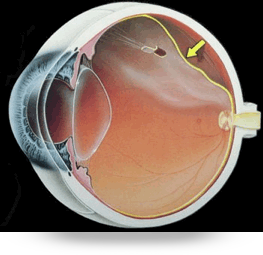

El queratocono se puede corregir con gafas, lentes de contacto rigidos, anillos o segmentos intracorneales, crosslinking y transplante de córnea en su fase final.

El queratocono es una enfermedad de la córnea la cual causa mala visión de forma progresiva.

Durante la evolución del queratocono nuestra córnea adopta una forma cónica irregular debido a la alteración de su estructura interna.

Los principales síntomas anatómicos del queratocono son el adelgazamiento de la córnea en su zona central o paracentral, la córnea se vuelve más fina conforme se va desarrollando el queratocono, y una continua elevación de esta zona, que provoca cada vez peor visión a medida que el queratocono avanza.